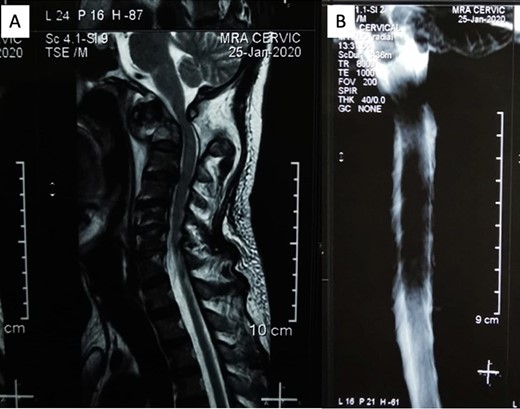

Before the operative procedure was performed, the patient was immobilized using a Philadelphia collar. The patient was then induced under general anesthesia, with fiberoptic intubation used for intubation. We shaved and sterilized the craniocervical region using an antiseptic agent and ensured proper draping. A midline skin incision was made subperiosteally, exposing the area from the inion to the C3 region, with a width of ~6 cm (Fig. 3A). Special attention was given when dissecting around the C1 region to avoid potential vascular injuries. Drilling was performed on the occipital bone to create a flat surface, and a high-speed drill was used to insert an occipital screw with a length of ~10 mm. Lateral mass screws were utilized for cervical instrumentation, and the size of the midline occipital plate was chosen to align with the rod attachment points, which were then fixed with the lateral mass screws (Fig. 3B). During the screw placement process, we used a C-arm and our anatomical knowledge to ensure proper screw trajectory. We did not utilize electrophysiological monitoring during the operative procedure as we did not have that facility in our institution. Bone graft was not used in this patient. Wound closure was meticulously performed layer by layer, with careful reconstruction of the paraspinal muscles. Following the operative procedure, a soft collar was applied postoperatively to the patient’s neck.

(A) Midline skin incision was marked to expose from occipital bone to C3 level and (B) occiptocervical fixation using an occipital plate that fixated on occipital squama connected by a surgical rod through the C4 on both sides.